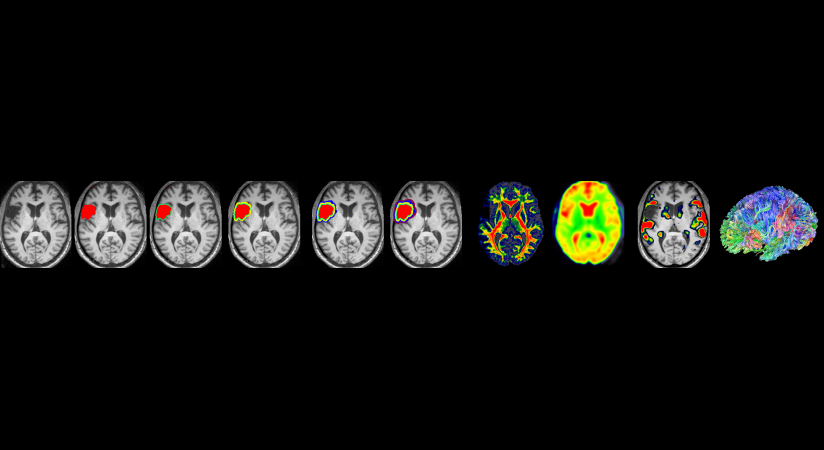

McCausland Center for Brain Imaging

- 3T Magnetic Resonance Imaging